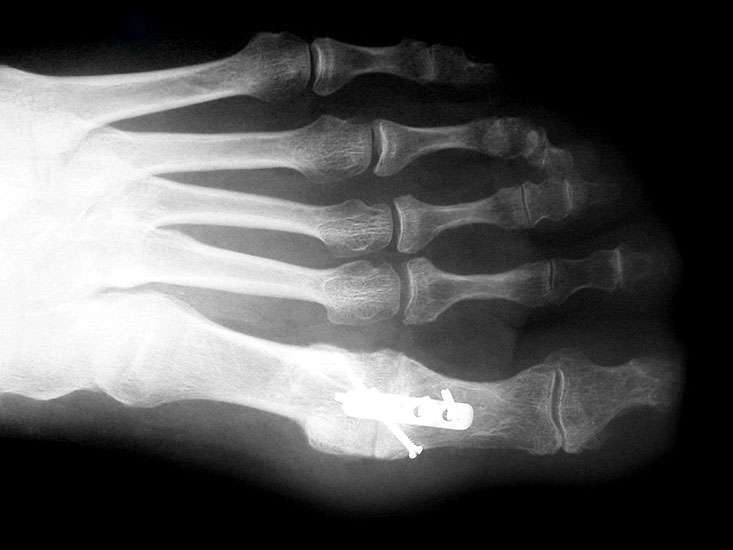

Der Zugang bei der Arthrodese mit den konischen Fräsen erfolgt von dorsal, da das Gelenk dadurch besser exponiert werden kann. Die Streckersehnen werden nach lateral weggehalten. Das Grundglied wird nach der Osteophytenabtragung und der Kapsulolyse scharnierartig nach plantar gekippt. Zentral in die Knochen eingebrachte Führungskirschnerdrähte ermöglichen das Fräsen und Abrunden des Kopfes und das Modellieren der kongruenten Grube an der Zehenbasis. Die Definition der idealen Zehenposition erfolgt wiederum mit einer flachen Unterlage. Diverse Fixationstechniken sind beschrieben 3940. Wir fixieren die Arthrodese mit einer Platte 2,0 (Abb. 9-12) oder 2,7, da mit den kleinen Implantatdimensionen bei Bedarf mehrere unterschiedliche Schraubenpositionen möglich sind.